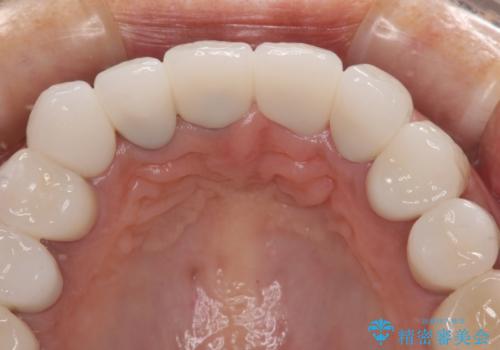

20年以上前から、むし歯になったり詰め物が欠けたりする度に部分的に処置を行ってきたそうですが、この際統一感のある前歯にしたいとのことで、上顎前歯9本をオールセラミッククラウンによる補綴治療を行うこととしました。

色調が統一されるだけでなく、歯肉ラインに見えていた茶色の境目も綺麗に改善されました。